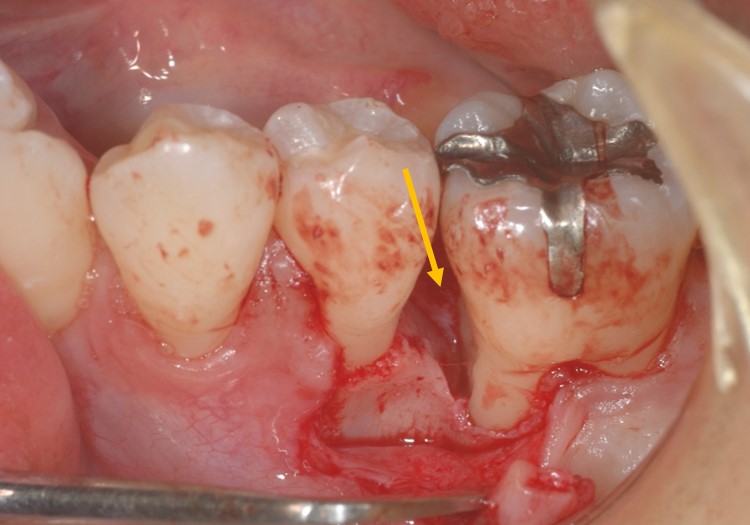

下写真は術前です。オレンジ矢印部分に6mmの歯周ポケットが存在します。

実際に歯肉を剥離したのが下写真です。オレンジ部分に骨吸収(歯周病で骨が喪失した部分)が確認できます。